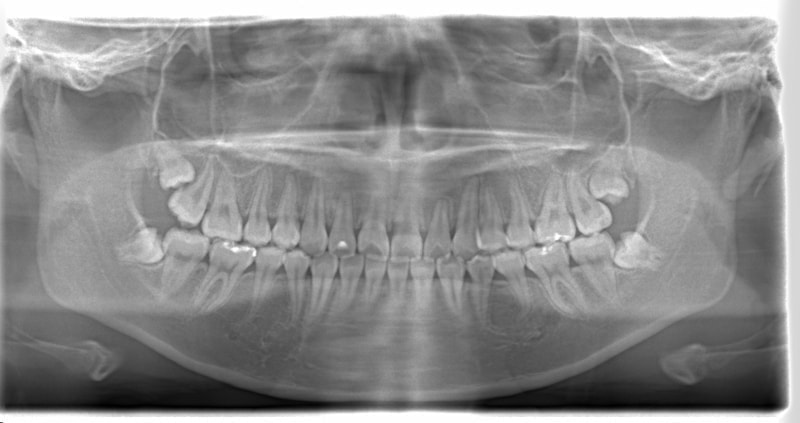

左上3番左下5番埋伏歯

治療後(1年12ヶ月後)